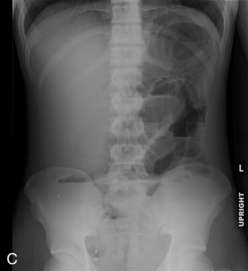

Management

The three phases of management of the child with GI bleeding are resuscitation, specific diagnosis, and specific treatment. A diagnostic algorithm for upper GI bleeding is presented in Fig. 14-9.

image

Fig. 14-9 Diagnostic algorithm for upper gastrointestinal (GI) hemorrhage. PPI, Proton pump inhibitor; PUD, peptic ulcer disease.

(From Arensman RM, Browne M, Madonna MB: Gastrointestinal bleeding. In Grosfeld JL, O'Neill JA, Coran AG, Fonkalsrud EW, editors: Pediatric surgery, ed 6, Philadelphia, 2006, Mosby.)

During resuscitation and replacement of intravascular volume, nursing observations may help to determine the source of the child's bleeding. If saline lavage through a nasogastric tube reveals grossly bloody or red-tinged aspirate, ongoing upper intestinal bleeding is present. Nursing interventions during resuscitation of the child with GI bleeding are summarized in Box 14-1.